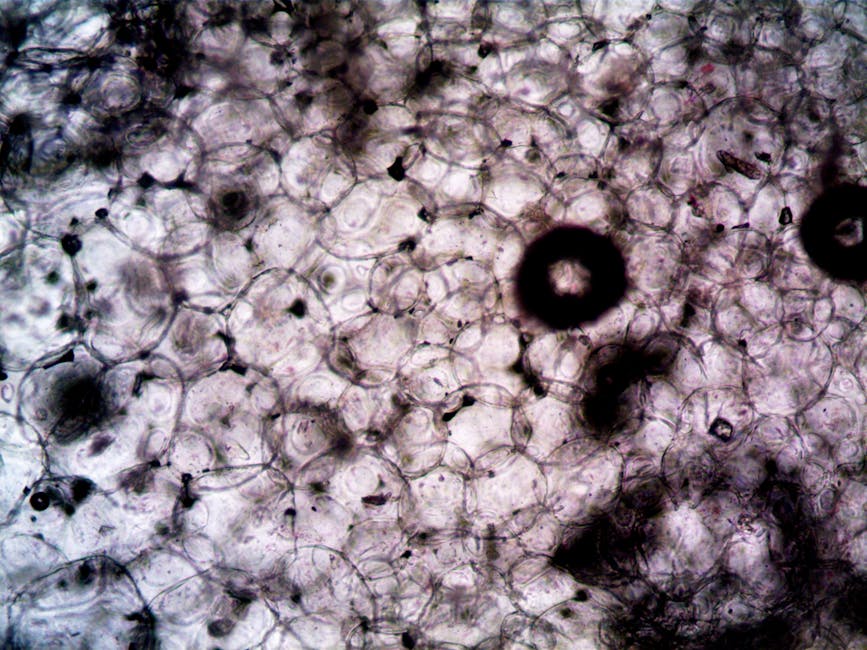

Breakthrough Study Reveals Secret to Resistant Pancreatic Cancer Cells

New research sheds light on the survival mechanism of pancreatic cancer cells